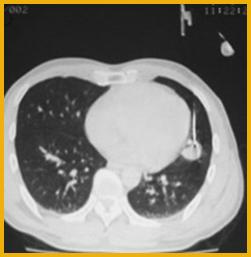

经皮肺穿刺活检为微创诊断肺部疾病的一种方法。许多纤维支气管镜未能取得病理诊断的患者在我科利用经皮肺穿刺活检术得到确诊,弥补了纤支镜的不足,为患者的进一步科学合理治疗提供了支撑。其适应证为:1、肺内结节、纵隔肿块;2、胸壁或胸膜的肿块;3、局灶或多发的肺内突变,感染菌种不明;4、不能手术,但须确定病理类型的肺内恶性病变者。

我院拥有吉安市唯一一台64排128层CT,可进行CT骨三维重建、CT血管造影等。同时拥有DSA血管造影设备(大C臂及中C臂等),为我院开展深静脉造影、内脏血管造影及治疗等奠定了基础。

我科对胸部肿瘤如肺癌、食管癌、乳腺癌等开展了以手术、立体定向放疗、化疗(含新辅助化疗及术后化疗)、靶向治疗、调节免疫等五位一体的综合治疗。尤其是开展了非小细胞肺癌EGFR基因检测、乳腺癌HER-2免疫组织化学检测及靶向治疗,以小创伤给给患者带来大好处。例如,在肺癌治疗上,利用低剂量CT在微小结节型肺癌诊断基础上,采用胸腔镜手术,使患者达到微创、高效诊治。在常规化疗一、二线化疗的同时紧跟国际指南,采用小分子表皮生长因子受体(EGFR)酪氨酸激酶抑制剂,如吉非替尼(Gefitinib,Iressa,易瑞沙)、厄洛替尼(Erlotinib,Tarceva,特罗凯)对EGFR突变阳性患者进行靶向治疗,大大提高了患者远期生存率及生活质量。在乳腺癌治疗上,我科积极开展乳腺癌前哨淋巴结活检、保乳手术、乳房再造术等,同时根据患者情况,采用规范化疗、内分泌治疗及靶向治疗,取得了不凡的成绩。